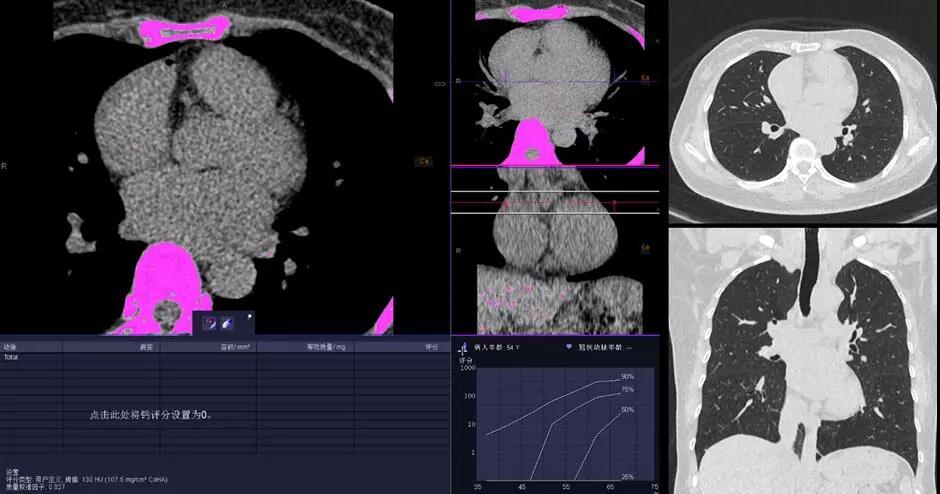

2.冠心病和腫瘤早期檢測(cè),胸片劑量的CT掃描,徹底實(shí)現(xiàn)心肺疾病CT篩檢的常規(guī)臨床化。只需要一次胸片檢查的輻射劑量,即可完成高分辨率的肺部成像和冠脈成像;在極低的輻射劑量下同時(shí)可以保持優(yōu)秀的對(duì)比信噪比(CNR),與傳統(tǒng) CT 相比輻射劑量減少達(dá)90%。配合Stellar Infinity 全息光子探測(cè)器優(yōu)異的低對(duì)比探測(cè)能力,使 SOMATOM Force成為隱匿性病變?cè)缙跈z測(cè)的理想設(shè)備。為無癥狀高危患者的檢查設(shè)定了一個(gè)新的檢查標(biāo)準(zhǔn)。這無疑將改寫CT掃描的歷史。

△KV純譜技術(shù)高端體檢一站式體檢——鈣化積分+肺一站式檢查